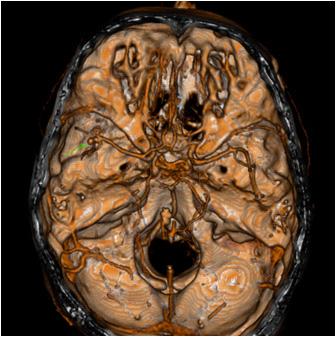

Materials and Methods : 90 Patients were selected during the study period as per the inclusion and exclusion criteria. Clinical scoring was done by NIHSS (National Institute of Health Scoring System). CT (Computed Tomography) scan of brain and MRI (Magnetic Resonance Imaging) Brain with DWI (Diffusion Weighted Image) extension was done. EEG findings on admission of morbidity was done by Modified Rankin Score on follow up after 1 month was noted. EEG findings after 1 month was noted on follow up. Assessment Clinical correlation was compared with EEG changes. All the data were collected and analysed by statistical software SPSS version 20.

ANALYSIS AND RESULTS

In our study most of the patients were in the age group of 61-70 years (45.6%), followed by the 51-60 years age group. Range of age was 51-85 years. Females were 44.4% and Males were 55.6% of the study-population. MRI of Brain with DWI extension revealed - 63.3%, 14.4%, 4.4% of the cases had MCA territory infarction, Multi-infarct state, ACA territory involvement respectively. On admission, 58.9%, 18.9%, 14.4%, 7.8% of the cases showed Normal EEG, Focal, Diffuse slowing and Multifocal slowing respectively. During follow up at 1 month, 91.8% of the cases showed Normal EEG, Focal and Diffuse slowing was noted in 4.1% cases each. The mean MRS after 1 month for abnormal and normal EEG on admission was 4.30 and 3.68 respectively, p value being 0.024 (significant). Among the abnormal EEG on admission the mean values of MRS were 3.29±0.59 and 5.77±0.44 in cases with focal slowing and diffuse slowing respectively, with p value of <0.001 (significant). The mean values of MRS were 3.36±0.8, 4.0±0, 5.0±0 in cases with normal EEG, focal slowing and diffuse slowing of EEG on follow up, with the p value of 0.006 (significant). In our study all Normal EEG on admission were focal lesions. Among abnormal EEG findings 64.86% and 35.14% were with focal lesions and Multi-infarct state respectively with p value being <0.001 (significant). During follow up all of the normal EEG was of patients with Focal lesions and abnormal EEG findings were equal among focal lesions and multi-infarct state with p value of <0.001 (significant). Our study shows 73.58% and rest of normal EEG on admission were with Subcortical lesions and Unifocal lesions respectively. Among the abnormal EEG 66.67%, 4.17% and rest were of unifocal, subcortical and multifocal lesions respectively, with p value <0.001 (significant). Our study showed 96.43% of cases with MCA territory infarct had normal EEG after 1 month in comparison to

68.42% on admission, which was statistically significant. Also 3.57% of cases with MCA infarct showed EEG with focal slowing after 1 month against 19.3% on admission, which was also considered significant. Significant improvement was also found in case of multifocal slowing of EEG in MCA territory infarct. 90.0% of PCA territory infarct showed normal EEG after 1 month against 54.55% on admission, with a significant p value. 10% of them had focal slowing after 1 month in comparison to 45.45% on admission, which was statistically significant. 91.67% of cortical lesions showed normal EEG after 1 month in comparison to 37.84% on admission with p value of <0.001 (significant). 8.33% of them showed focal slowing after 1 month in comparison to 43.24% on admission, which was statistically significant. Significant improvement change in multifocal slowing of EEG in them was also found. This study showed good clinical outcome in patients with ACA, MCA and PCA infarct. Whereas, Pontine infarct and those with Multi-infarct state showed very poor clinical outcome with high mortality. The p value of this correlation was found significant. The mean MRS after 1 month for ACA, MCA, PCA, Multi-infarct and pontine infarct respectively were 3±0, 3.44±0.91, 3.73±1.19, 5.77±0.44, 6±0. Multi-infarct state was associated with high mortality rate, whereas, cortical or subcortical lesion showed good clinical outcome according to MRS after 1 month which for cortical, subcortical and multi-infarct state respectively were 3.54±0.77, 3.7±1.34, 5.77±0.44. The p value of this study was also significant (Tables 1 & 2).

Table 1 — Comparison of EEG findings on admission and after 1 month according to site of infarct

Table 2 — Comparison of EEG findings on admission and after 1 month according to site of lesion